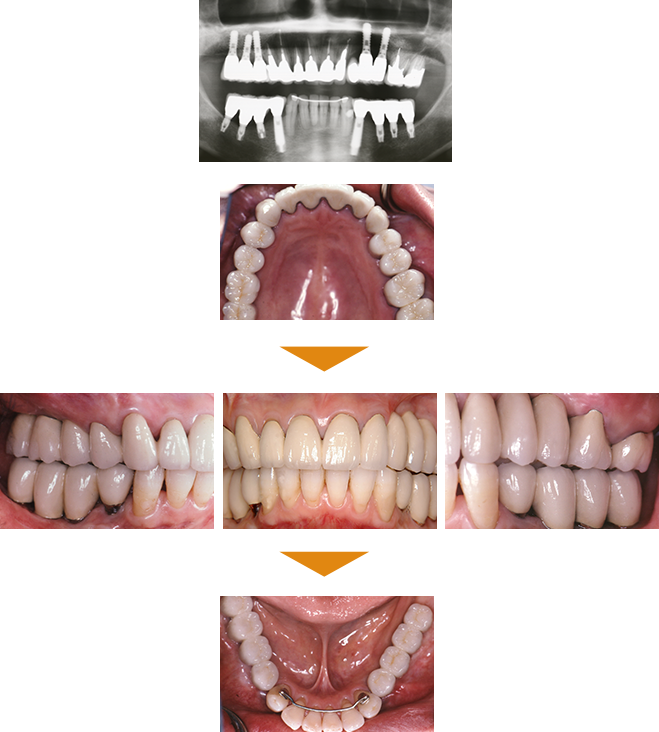

症例3

奥歯(臼歯) インプラント埋入

|

| 治療期間 | 約4カ月 |

|---|

| 費用 | 6,545,000円(税込) |

|---|

※状態により、骨補填等別途で費用が発生する場合もございます。